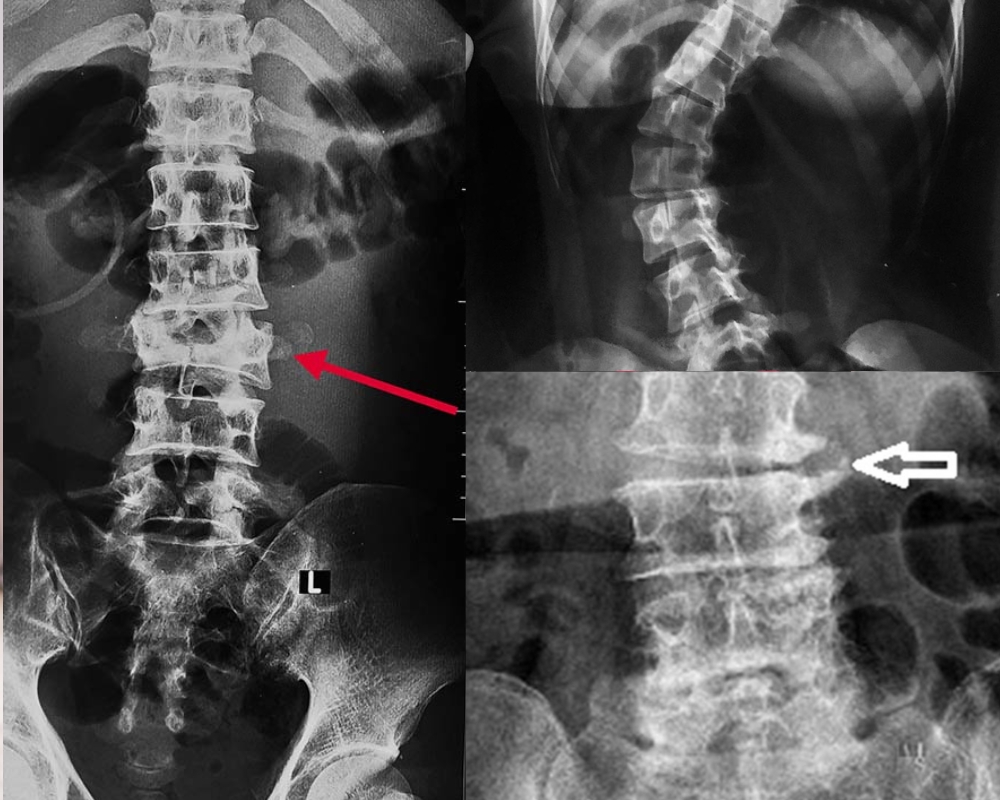

- Thoái hóa cột sống lưng

Cột sống lưng nằm giữa cột sống cổ với xương cụt gồm 12 đốt từ L1 - L12.

Dấu hiệu nhận biết thoái hóa:

+ Đốt sống bị nứt vỡ, mài mòn

+ Hình thành gai xương ở rìa đốt sống

+ Dây thần kinh bị chèn ép

+ Trượt đốt sống thắt lưng

+ Cột sống bị dị dạng